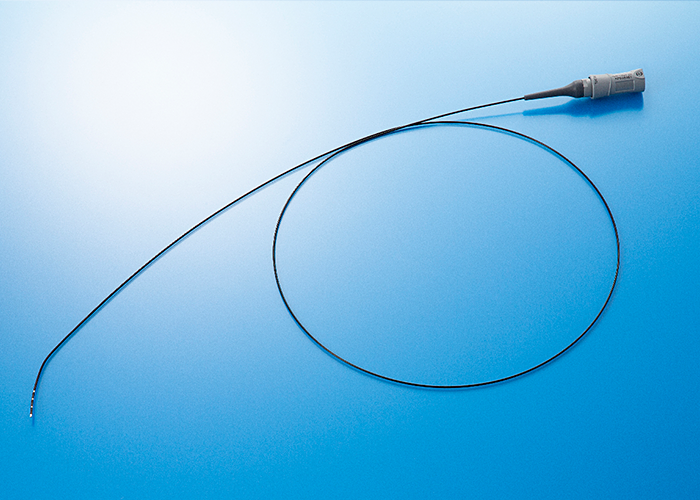

Fix Diagnostic Catheter

- 販売名

- カネカ電極カテーテル

- 医療機器承認番号

- 22900BZX00308000